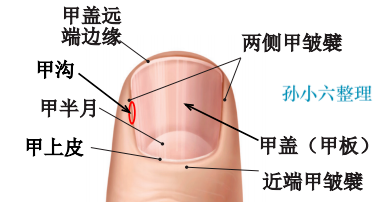

趾甲解剖